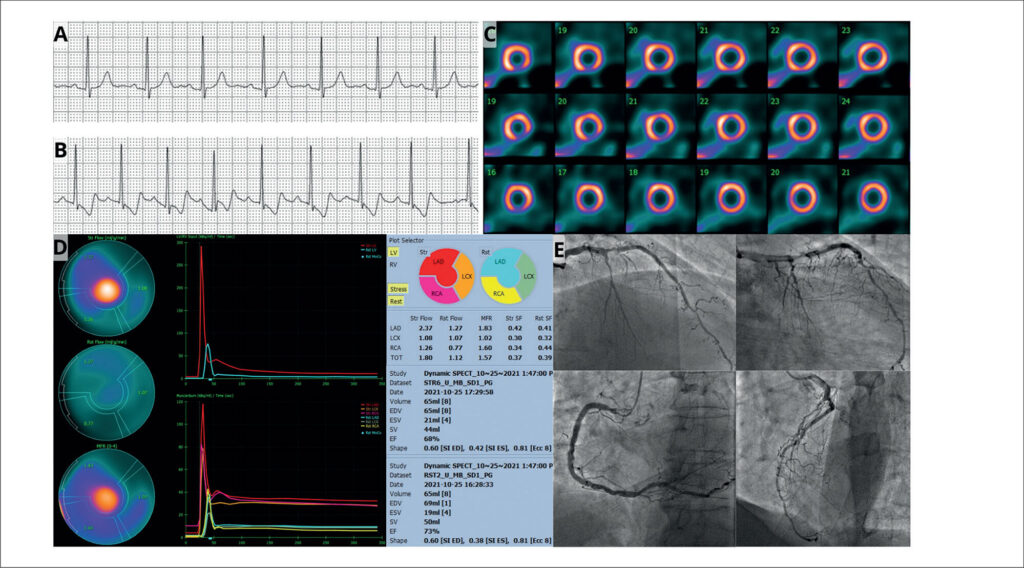

O presente relato de caso apresenta análise da perfusão do miocárdio em um paciente masculino assintomático de 67 anos com doença arterial coronariana (DAC) conhecida e múltiplos fatores de risco. Enquanto a perfusão do miocárdio por tomografia computadorizada por emissão de fóton único (SPECT) revelou área de isquemia do miocárdio de 5%, a gama câmara utilizando detectores de telureto de cádmio e zinco (CZT) revelou uma reserva de fluxo miocárdico (RFM) global reduzida (1,57). A cinecoronariografia coronária confirmou doença multiarterial extensa, incluindo uma lesão de 80% na artéria descendente anterior (ADA) e uma oclusão da artéria circunflexa (ACX), achados não totalmente reconhecidos pela perfusão do miocárdio por SPECT. O presente caso demonstra a importância da avaliação da RFM, particularmente usando a tecnologia CZT, na identificação de DAC significativa que pode ser subestimada pelos métodos tradicionais de SPECT. Isso destaca o potencial da CZT para fornecer informações funcionais mais abrangentes, melhorando a estratificação de risco e potencialmente influenciando o manejo do paciente em casos complexos de DAC suspeita ou conhecida.